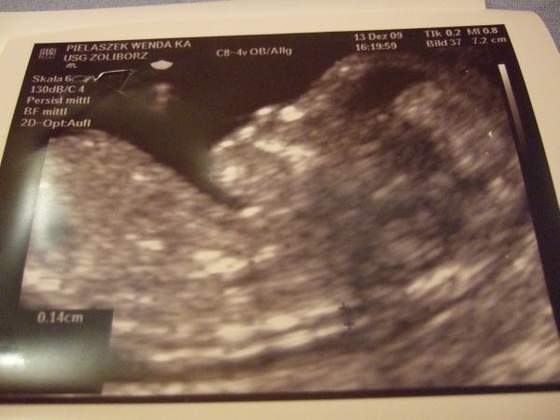

Super maluszki:-)